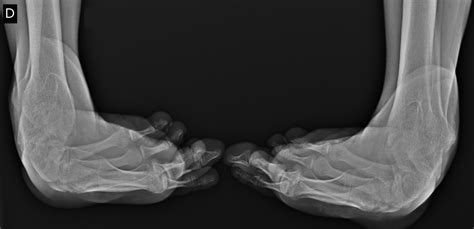

While often associated with infancy and early childhood development, Talipes Equinovarus in adults represents a complex clinical scenario that can significantly impact a person’s mobility, comfort, and overall quality of life. Commonly known as clubfoot, this condition involves a structural deformity where the foot is twisted inward and downward. When this condition persists into adulthood—either as a result of untreated congenital cases, relapse after initial treatment, or secondary causes like neurological disorders—it requires specialized orthopedic intervention to restore function and alleviate chronic pain.

The term Talipes Equinovarus is derived from Latin, where "talus" refers to the ankle, "pes" to the foot, "equinus" to the horse-like position (plantar flexion), and "varus" to the inward inversion. In an adult patient, the foot may appear rigid, making it difficult to place the sole flat on the ground. This rigid deformity is not merely cosmetic; it changes the biomechanics of the entire lower limb, often leading to secondary complications in the knee, hip, and lower back due to compensatory gait changes.

Patients living with Talipes Equinovarus in adults often present with a distinct set of physical challenges. Because the foot is held in an abnormal position, the distribution of weight while walking is severely compromised. This leads to the development of painful calluses on the outer edge of the foot, which is the primary weight-bearing surface.